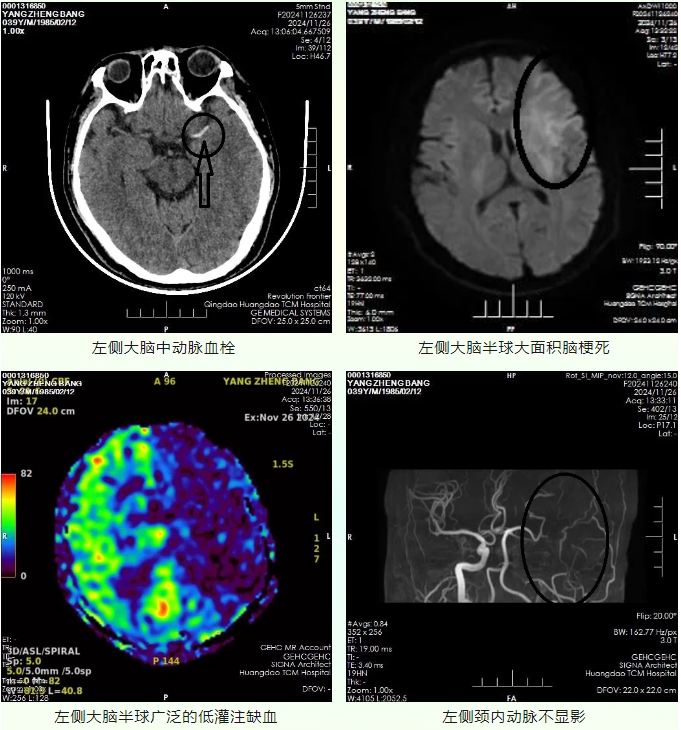

来青务工的赵先生现年39岁,入院前1.5小时被邻居发现躺在出租屋内,不能言语,右侧肢体无力,拨打120送至青岛西海岸新区中医医院急诊科。急诊脑CT示左侧大脑中动脉高密度影,初步诊断为大面积脑梗死,患者起病时间不详,急查磁共振检查,DWI示左侧大脑半球大面积脑梗死,左侧大脑半球存在广泛的低灌注缺血区,可予静脉溶栓治疗。

左侧大脑中动脉血栓

左侧大脑半球大面积脑梗死

左侧大脑半球广泛的低灌注缺血

左侧颈内动脉不显影

MRA示左侧颈内动脉未显影,属责任大血管病变,符合介入治疗指征。因患者无亲属陪同,医护人员多方联系亲属、报备相关部门,开通绿色通道。予阿替普酶静脉溶栓治疗,完善脑血管造影备颅内动脉取栓治疗。